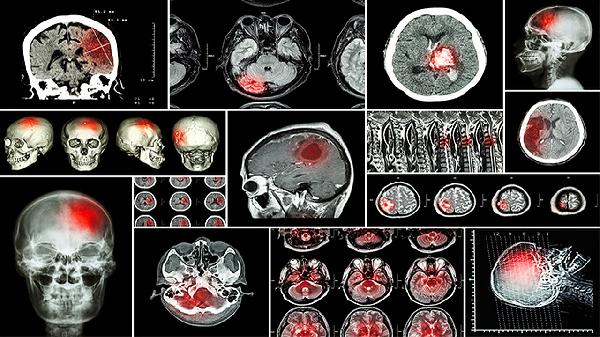

硬化性血管瘤怎么治比较好

尽早的手术治疗。术前术后要积极的抗感染治疗,根据医生的指导使用抗生素类药物来治疗。平时要注意不要吃辛辣刺激寒凉的食物。有什么问题去正规医院做个检查,可以及时采取措施。

硬化性血管瘤怎么办

硬化性血管瘤可通过手术切除、激光治疗、冷冻治疗、放射治疗等方式干预。硬化性血管瘤通常由血管内皮细胞异常增生、局部创伤、激素水平变化、遗传因素等...